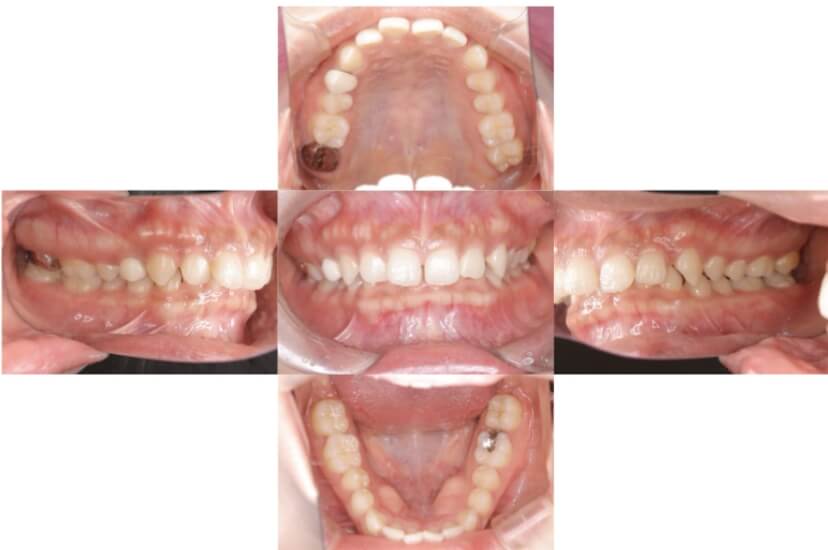

BEFORE

AFTER

上下顎叢生、反対咬合(上下の前歯のガタガタ、若干受け口)のケースです。

装置はラビアル(上下表側)で、上下顎の小臼歯を4本抜歯を行っています。抜歯したスペースを使って、上下の叢生改善と前歯の受け口の改善を行っています。

主訴 前歯のガタガタを治したい。

年齢・性別 45歳 女性

お住まいの地域 神奈川県川崎市

治療方針 抜歯スペースを利用して上前歯の叢生(ガタガタ)の改善と受け口の改善

抜歯部位 上顎左右第一小臼歯、下顎左右第二小臼歯

使用装置 ラビアル(上下表側)、顎間ゴム

治療期間 2年6か月

治療回数 20回